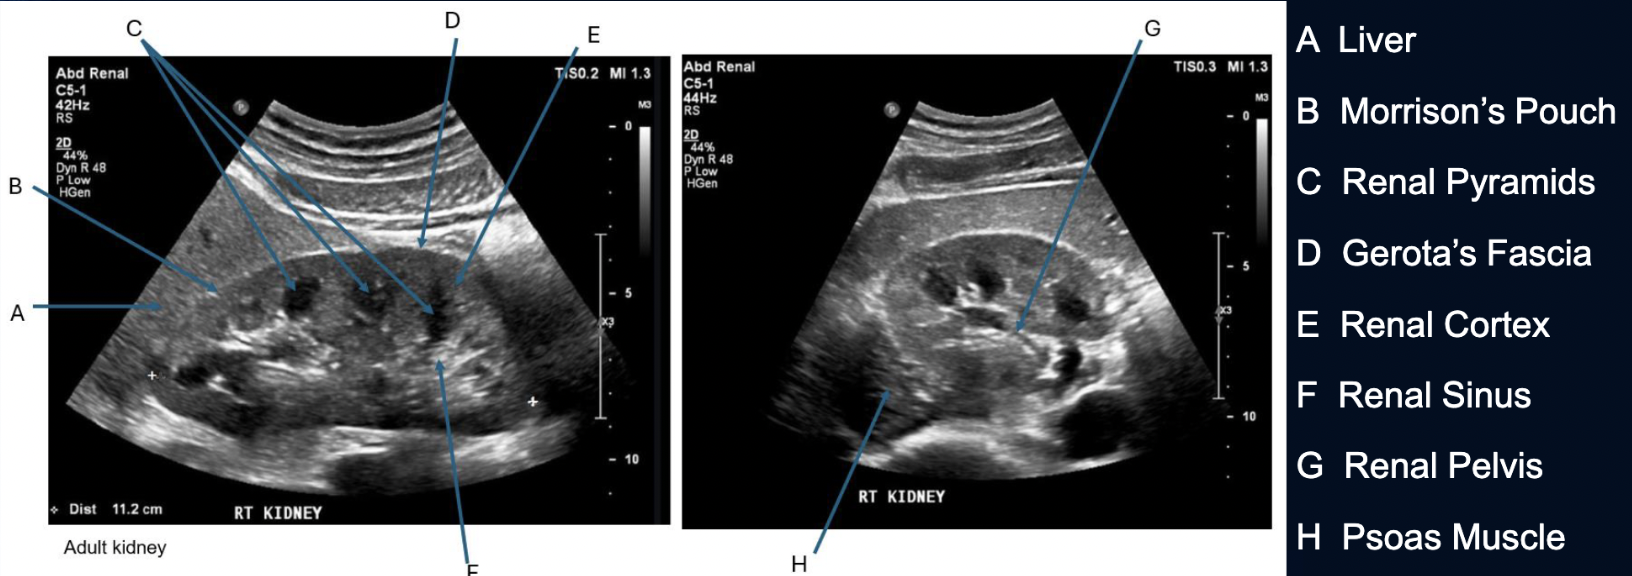

What is this?

Dromedary Hump